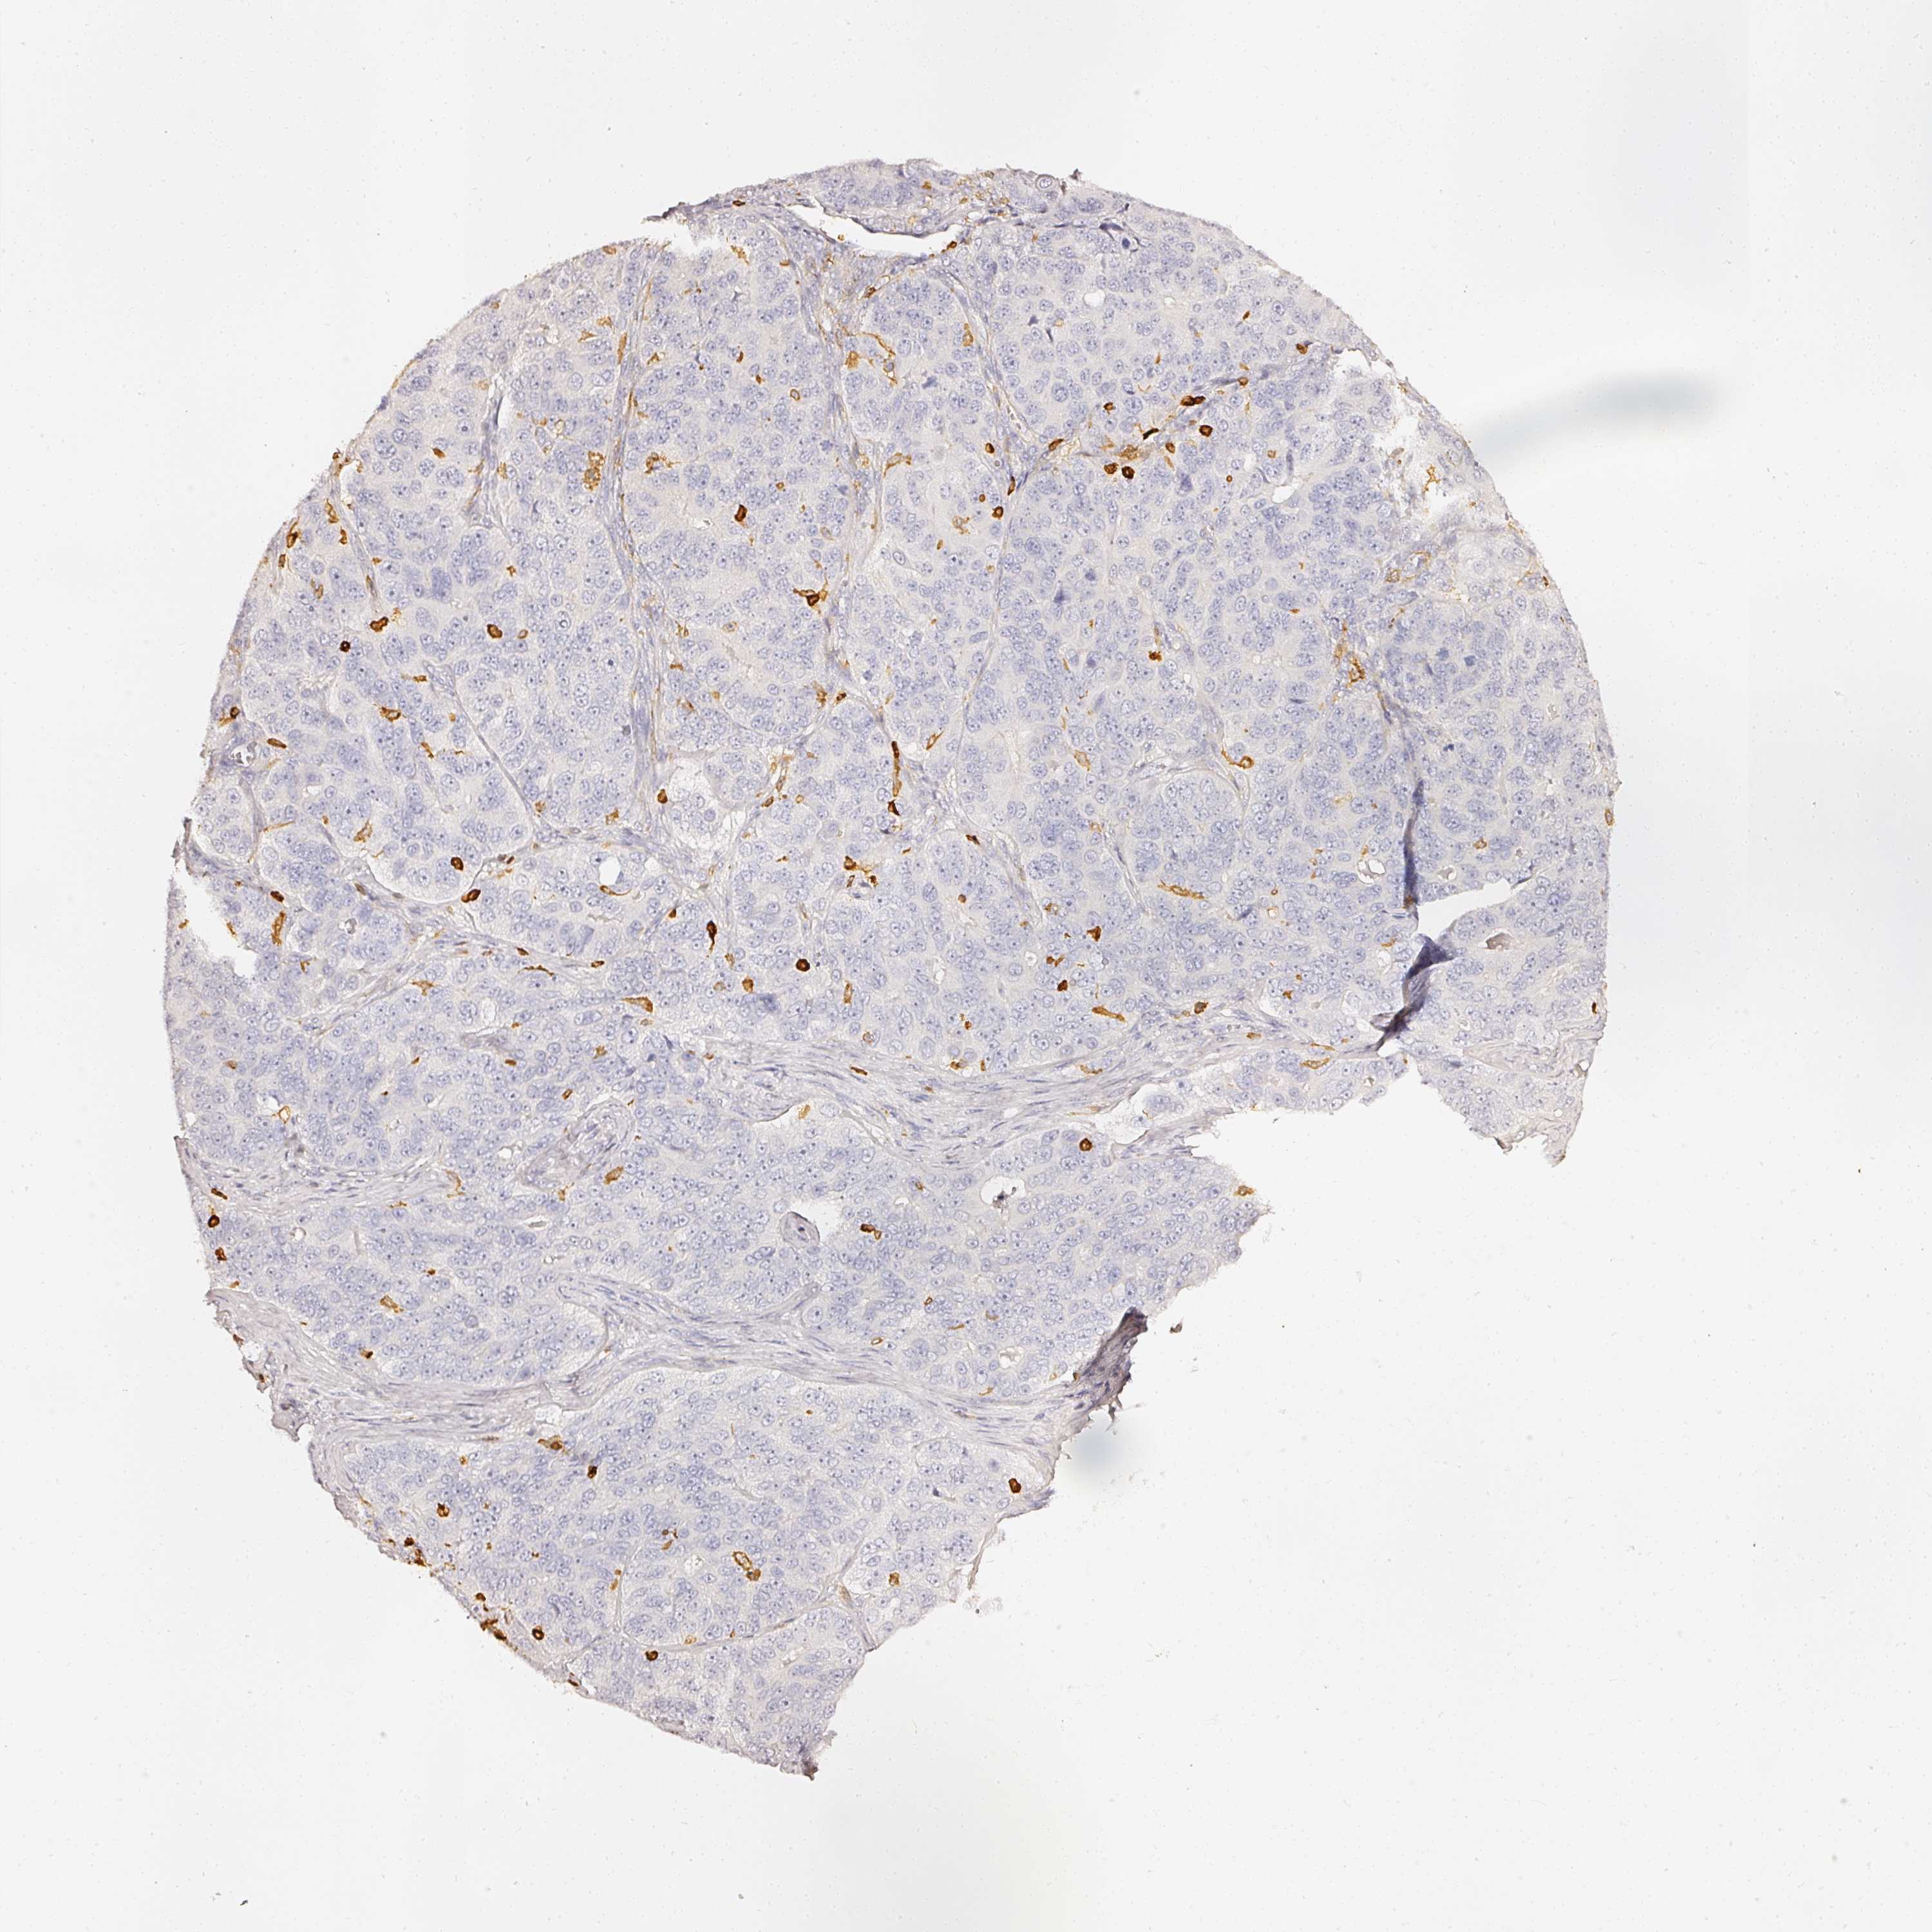

OVARIAN CANCER - Protein expressioni

A mouse-over function shows sample information and annotation data. Click on an image to view it in a full screen mode. Samples can be filtered based on level of antibody staining by selecting one or several of the following categories: high, medium, low and not detected. The assay and annotation is described here.

Note that samples used for immunohistochemistry by the Human Protein Atlas do not correspond to samples in the TCGA dataset.

Antibody stainingi

Antibody staining in the annotated cell types in the current human tissue is reported as not detected, low, medium, or high, based on conventional immunohistochemistry profiling in selected tissues. This score is based on the combination of the staining intensity and fraction of stained cells.

Each image is clickable and will lead to virtual microscopy that enables deeper exploration of all samples and also displays staining intensity scores, fraction scores and subcellular localization as well as patient and tissue information for each sample.

Antibody HPA018849

Cystadenocarcinoma, serous, NOS